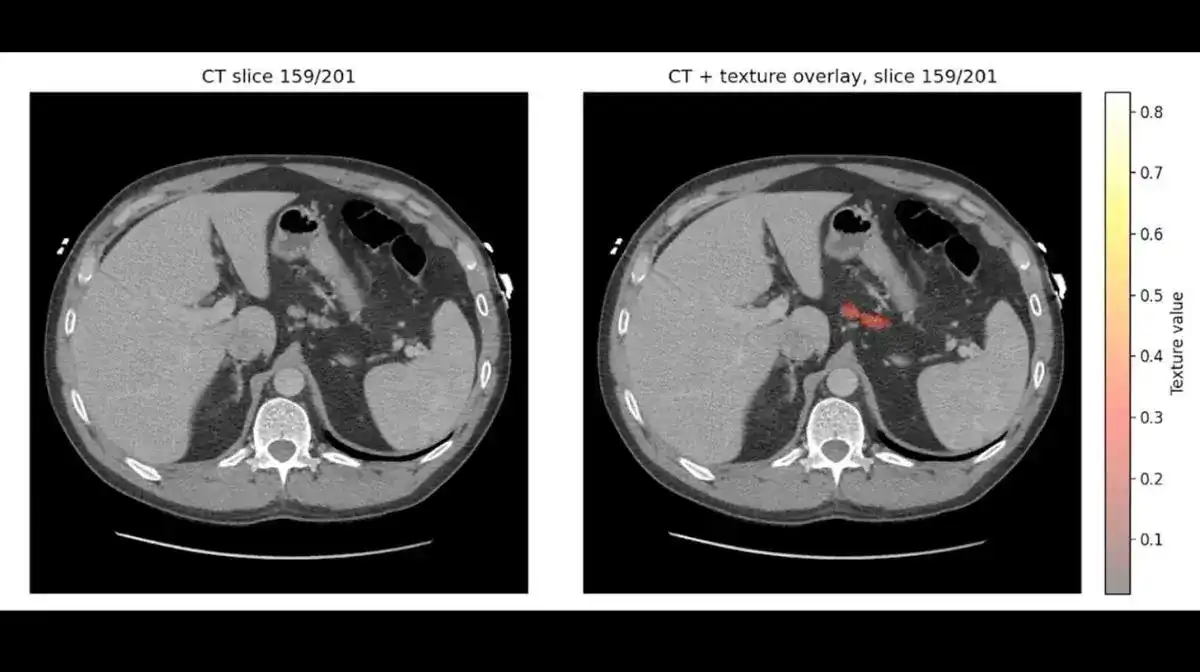

AI资讯:梅奥诊所发布了关于REDMOD的新数据,REDMOD是一种人工智能技术,能够读取标准CT扫描中不可见的组织模式,能够比医生通常发现胰腺癌的时间提前三年发现该疾病,并使专家诊断的准确性几乎翻倍。

细节如下:

• REDMOD审查了近2000份常规CT扫描,这些扫描在后续诊断前被专家初步判定为正常,但REDMOD早期发现了其中73%的病例。

• 在确诊前两年,差距进一步拉大,人工智能检测出的早期癌症数量大约是经验丰富的放射科医生的3倍。

该模型能够读取“数百个定量成像特征”、纹理以及结构模式,这些通常对人类放射科医生来说是看不见的。

为何重要:胰腺癌的五年生存率低于15%,因此早期诊断和治疗至关重要。

借助REDMOD对已有扫描结果的分析,人工智能的早期筛查能力有望成为常规护理的标准部分,而非增加系统复杂性的独立诊断步骤。